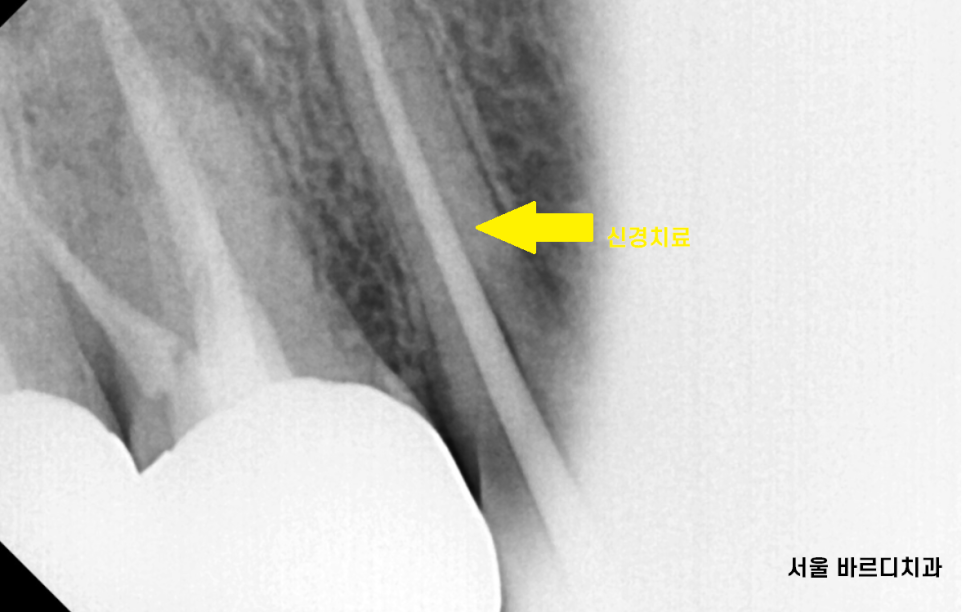

ct상에도 금이 확실히 보입니다!

다행인 것은 환자분은

수직으로 금이간 것이 아니라

비껴 갔습니다.

비스듬하게 한쪽 모퉁이만 금이 간 것으로 보이네요~

천만다행입니다.

우선은 무조건 뽑기보다

조심스럽게 치아 조각을 제거 후 신경치료 하여 써보기로

진단해드렸습니다.